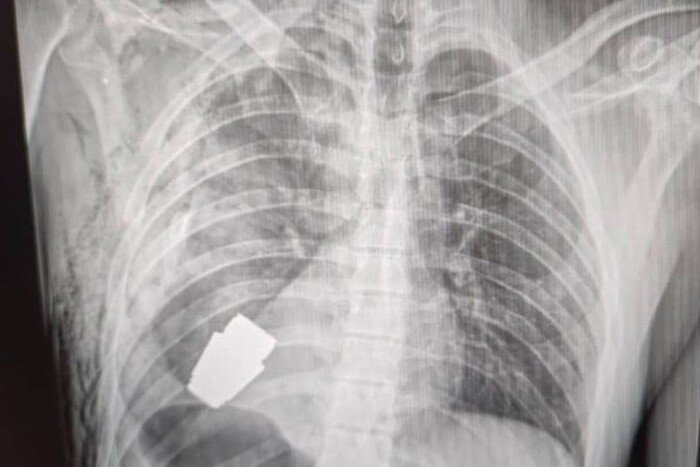

«Подивилися знімки, з’ясували, що в тілі снаряд. Рішення оперативно ухвалював безпосередньо Андрій Верба. Викликали саперів, вони відповідали за безпеку медперсоналу», – розповіла нам у коментарі про деталі Євгенія Слівко.Оперувати самостійно вирішив Андрій Верба – генерал-майор та досвідчений хірург ЗСУ. Операція відбувалася без електрокоагуляції.«Усе зшивалося вручну, оскільки граната могла детонувати в будь-яку хвилину», – пояснює Слівко.

Граната залишалася біля серця. За словами радниця, поранений був важким, але стабільним. Операція відбулася успішно, і військового вже відправили на реабілітацію та відновлення.